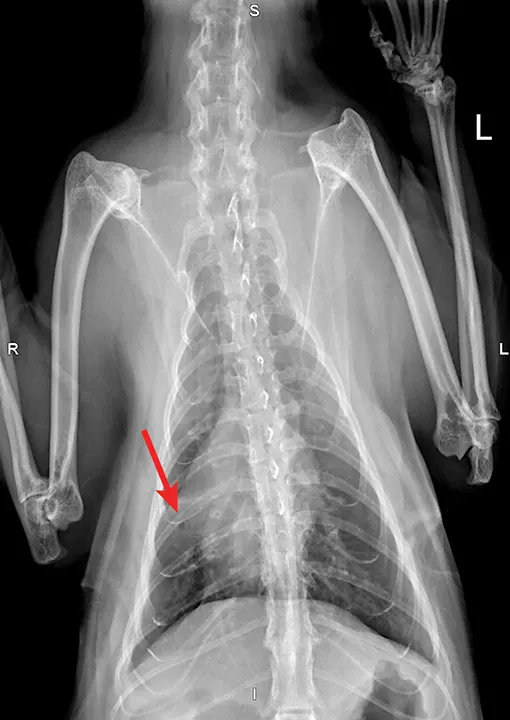

Overt cardiomegaly may be understated on radiographs because of changes in internal diameter that do not affect the overall cardiac silhouette. Vertebral heart score >9.3 supports a CHF diagnosis.1 Pulmonary venous congestion can be absent, and pulmonary arterial distension may be appreciated. The presence of pleural effusion with simultaneous pulmonary infiltrates is supportive of CHF (Figure 1).2

Congestive heart failure. Note the pleural effusion (arrows).